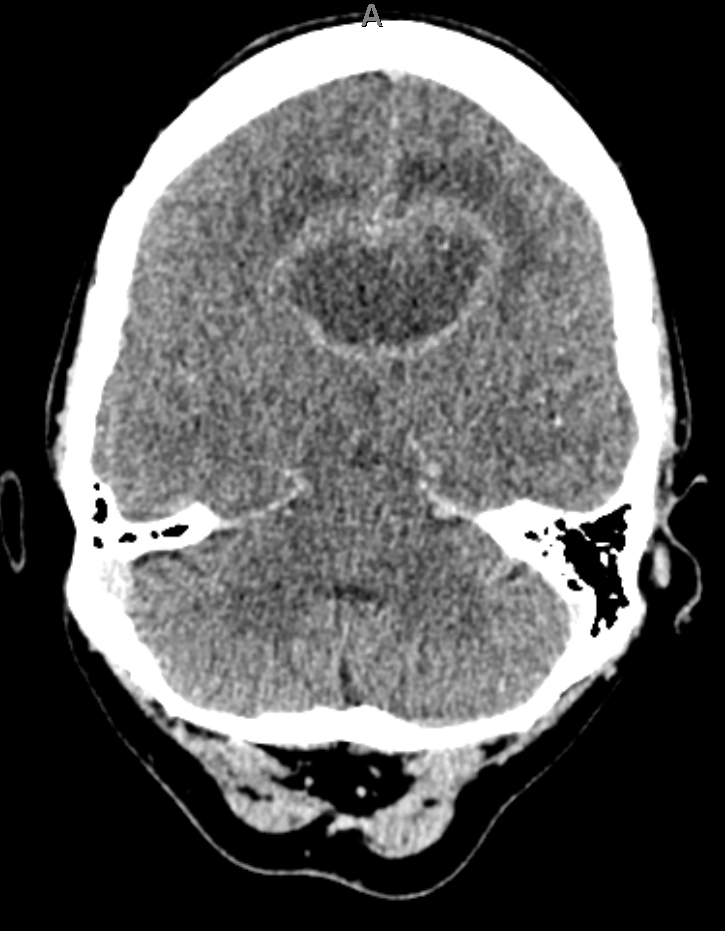

- CT: Enhancing deep lesions with surrounding oedema.

- MRI: Dense periventricular enhancing lesions, often homogeneously enhancing. May cross corpus callosum (โbutterflyโ). Dramatic but transient response to steroids ๐ฏ.

๐งพ Imaging Differential: Butterfly Lesion

- Glioblastoma multiforme (GBM).

- Primary CNS lymphoma (consider HIV/EBV).